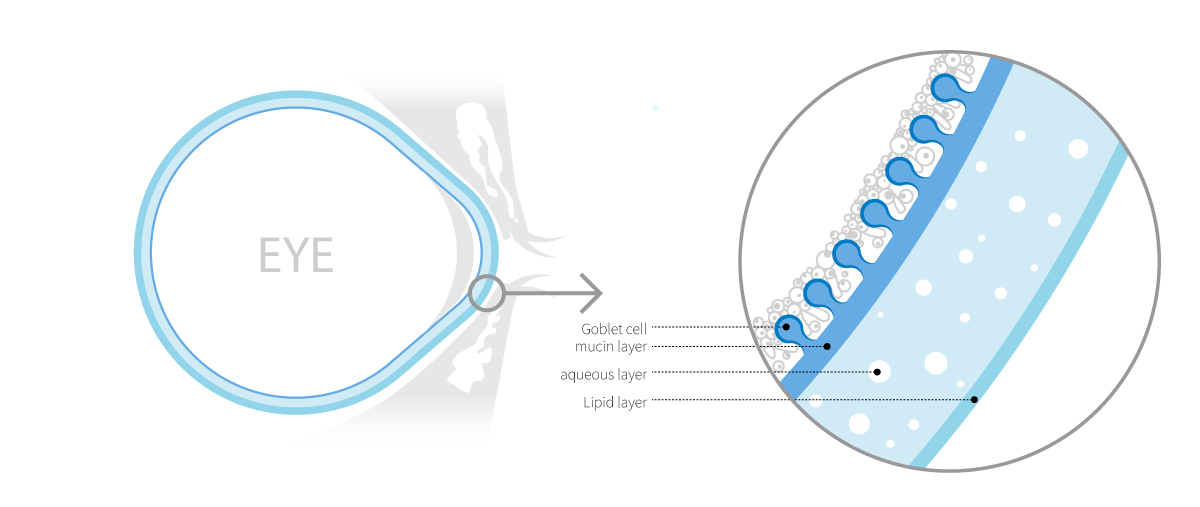

The Tear Film

Dry eye disease occurs due to abnormalities in the tear film and is often accompanied by ocular discomfort and keratoconjunctivitis.The tear film consists of the mucin, aqueous, and lipid layers, and accurate diagnosis of the affected layer is essential for appropriate treatment of dry eye disease.Although methods exist to evaluate each layer of the tear film, there is still a lack of adequate techniques to specifically assess the mucin layer.

Goblet cells, located in the conjunctival epithelium, secrete the mucin MUC5AC to form the mucin layer of the tear film. They play a key role in maintaining tear film stability and lubricating the ocular surface. When goblet cells are damaged or reduced in number due to inflammation or external stimuli, mucin secretion declines, leading to tear film instability and the onset of ocular surface diseases such as dry eye.